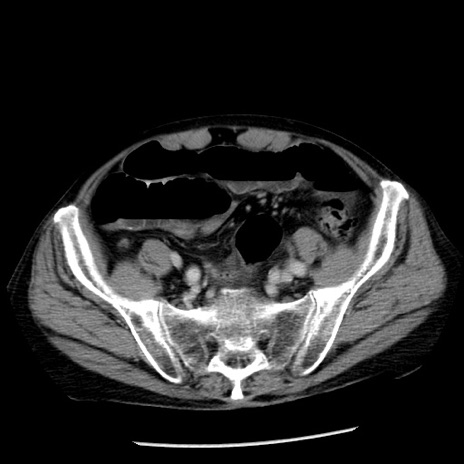

症例26(横断像)

【症例】80歳代男性

【主訴】嘔吐

【現病歴】昨晩2回嘔吐あり、今朝になっても嘔吐あり。来院。

【既往歴】胃潰瘍

【身体所見】意識清明、BT 37.6℃、BP 166/95mmHg、HR 100bpm、SpO2 97%、腹部:平坦・軟、腸蠕動音聴取良好、圧痛なし。

【データ】WBC 21900、CRP 1.46